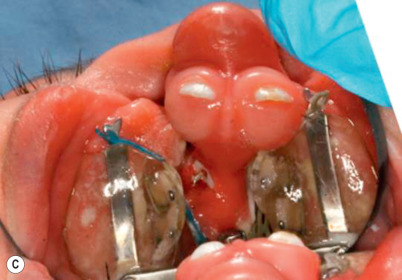

Active strategies include the Latham appliance ( Fig. 11.4 ) .

Figure 11.4

(A) Latham appliance; (B) prior to insertion of device; (C) 6 weeks following dentofacial orthopedic manipulation.